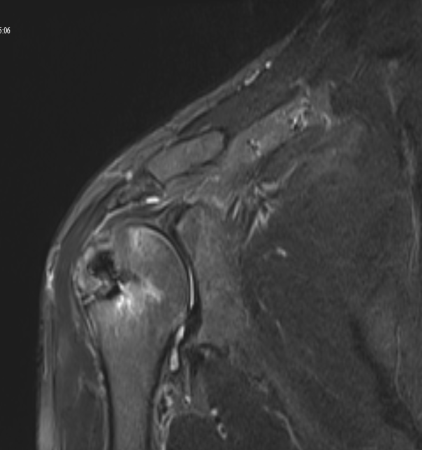

Postoperatif 3. ay MRI — tamir sonrası